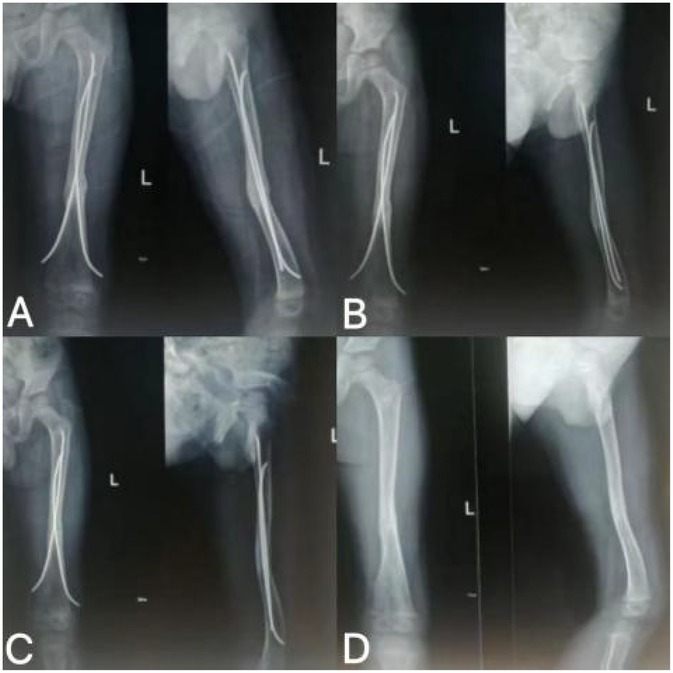

Figure 4. Follow-up imaging findings after rESWT treatment. (A) rESWT after 3 sessions of treatment; (B) rESWT after 7 treatments; (C) rESWT after 8 sessions of treatment; (D) Removal of intramedullary nail 13 months after fracture surgery.

The child exhibited a consistent trend of gradual improvement following the initial rESWT. At the 13-month follow-up visit, no abnormalities were observed in the child, and the previously implanted intramedullary nail was successfully removed. This outcome signifies that fracture healing and functional limb recovery both achieved an optimal state, with the overall positive trend maintained throughout the treatment and follow-up period (Table 2). Postoperative rehabilitation employed a phased weight-bearing progression: complete non-weight-bearing in the first postoperative week, beginning partial weight-bearing (10%–20%) at 2 weeks, and transitioning to full weight-bearing after 3 months (32). Radiological assessments at all time points confirmed successful bone healing. No adverse events related to rESWT, such as local bruising or exacerbated pain, were observed. The main limitation of this study lies in the lack of validated assessment tools for measuring range of motion or pain intensity (25).

Results: Post-rESWT, fracture lines blurred then disappeared, with clinical healing achieved and no complications. At 3-month follow-up, intramedullary nail was removed; the patient had 80% weight-bearing capacity, independent walking (mild gait asymmetry), and full weight-bearing recovery later.